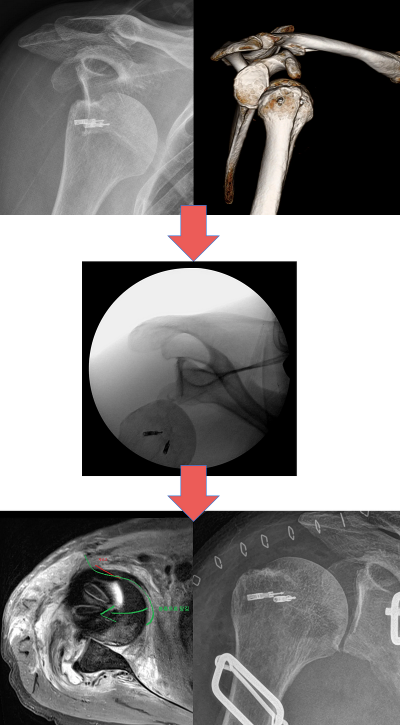

- 최근에 탈구된지 일주일이 넘은 것으로 추정된 환자분이 외래로 내원.

- 환자분은 본인 어깨가 전방탈구된 사실을 모르고 대증적 치료를 하고 있었음.

- 일주일간 증세 호전이 되지 않아서 근처 정형외과 의원 방문 후 "탈구되었다"라는 말을 듣고 내원.

- 수술방에서 진정 후에 도수정복을 1시간 이상 시도해보았으나 실패

C-arm상에서 어느정도까지는 정복이 되었으나 더 이상은 진행되지 않음.

- 결국 앞쪽 힘줄을 박리 한 다음에 정복 후에 다시 봉합을 시행함.

1*DlHOVPQrprEeZ1gbQPimSA.png 제가 경험한 케이스 입니다.

- 전신마취를 하지 않기 위해 최대한 도수 정복을 시도해보았으나 결국 실패하였습니다.

- 결국 전신마취 후에 관혈적 정복술 시행하였고, 현재 잘 유지 중입니다.